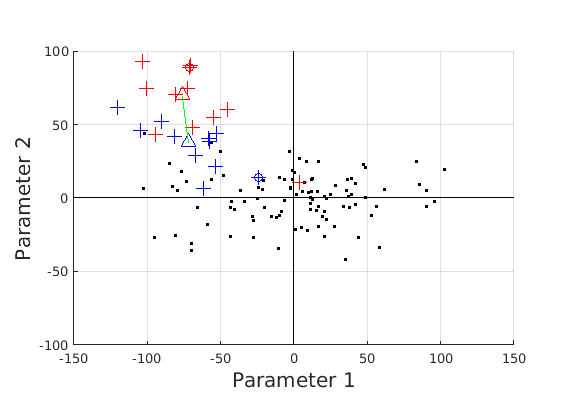

8 A case study of cranial profile model use for intervention outcome evaluation

In this section we take a sample of 25 boys, who are craniofacial craniosynostosis patients, 14 of which have undergone one type of corrective procedure (BS) and the other 11, another corrective procedure (TCR). Providing that the heads are sufficiently symmetrical and are amenable to ellipse fitting, we can parameterise all of these patients’ heads using our scale-normalised craniofacial profile model (2D model with face cropped out). We can then plot their pre-operative and post-operative parametrisations and compare them with the parameterisations of the 100 training examples. The expected result is that the parameterisations should show the head shapes moving nearer to the mean of the training examples. It also reveals which of the dominant modes of shape variation are most affected. The results are shown in figures 31 and 32.

For the TCR patient set, the Mahalanobis distance of the mean pre-op parameters (red triangle in Fig. 32) is 4.647, and for the mean post-op parameters (blue triangle) is 2.439. For shape parameter 2 only these figures are 4.354 and 2.439. We note that most of this change occurs in parameter 2, which corresponds to moving height in the cranium from the frontal part of the profile to the rear. In these figures we excluded one patient, who preoperatively already had a near-mean head shape (see red cross near to the origin in Fig. 32, so any operation is unlikely to improve on this (but intervention is required in order to relieve potentially damaging inter-cranial pressure).

It is not possible to make definitive statements relating to one method of intervention compared to another with these relatively small numbers of patients. However, the cranial profile model does show that both procedures on average, lead to a movement of head shape towards the mean of the training population. An example of analysis of intervention outcome for a BS patient is given in Fig. 33 and a TCR patient is given in Fig. 34. The particular example used is highlighted with circles on figures 31 and 32 to indicate pre-op and post-op parametrisations. To our knowledge this is the first use of statistical 3D craniofacial shape models in a clinical study.